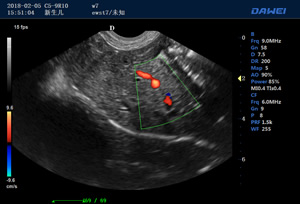

S90高端推車多普勒獸用彩超-動物寵物B超儀掃描圖 S90動物寵物B超儀檢測圖 S90多普勒獸用彩超